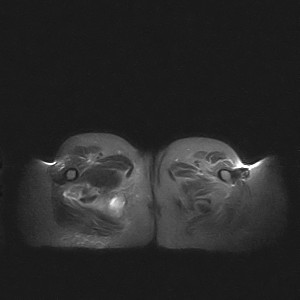

图像太差了 1、右侧臀肌旁脓肿? 建议增强 2、左侧股骨头坏死并半脱位

1、左侧股骨头坏死并髋关节半脱位;

2、右侧臀肌感染,(可能褥疮所致)